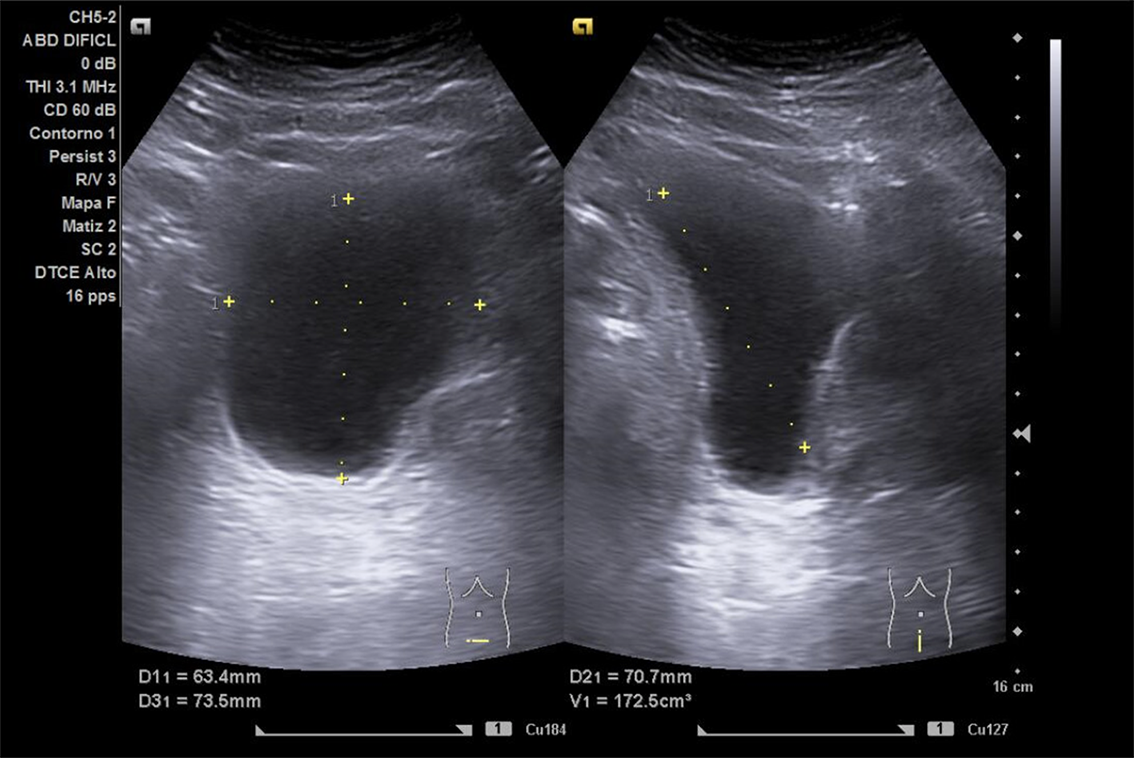

Se realiza ECO POCUS en la que se aprecia riñón derecho de morfología y tamaño normal. Riñón izquierdo con hidronefrosis grado III. A nivel de vejiga, bien replecionada se aprecia masa a nivel de pared izquierda adyacente a unión ureterovesical de 1.8 x 2,7 cm Ausencia de jet izquierdo.

Se realiza UroTAC en la que se aprecia masa infiltrante a nivel ureterovesical izquierda de 3,1 cm de diámetro mayor.